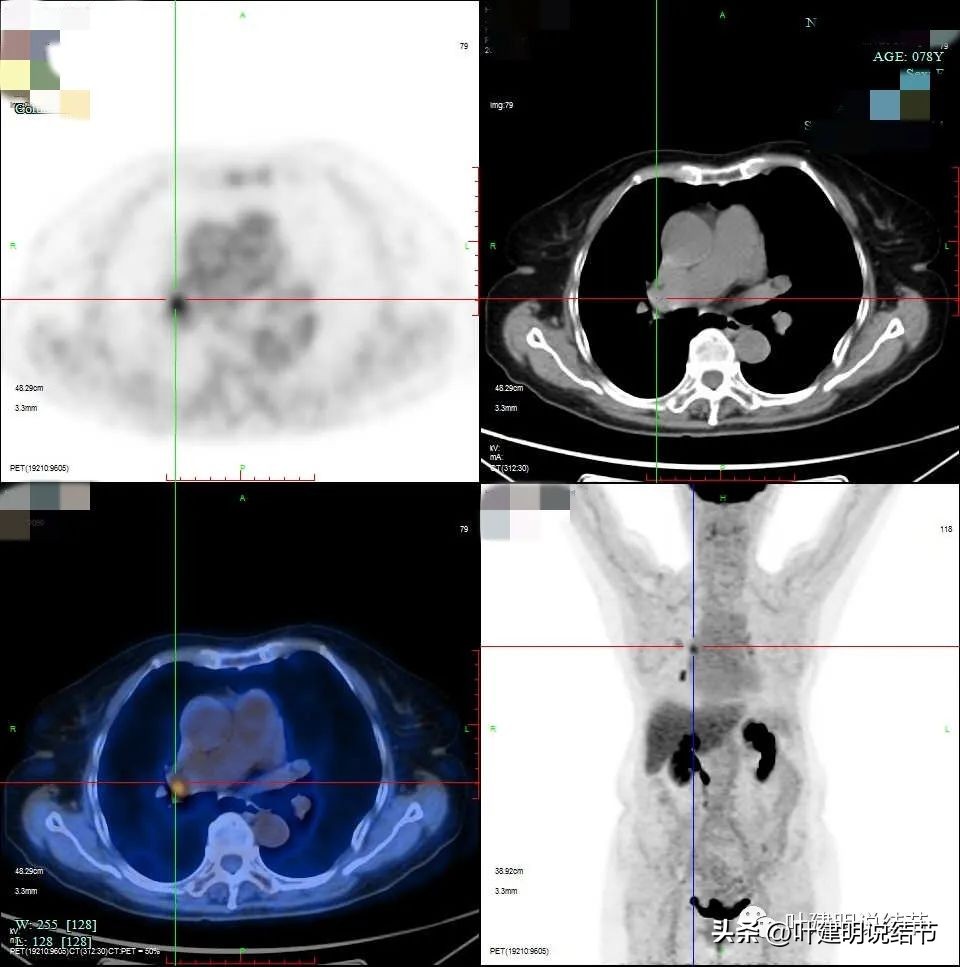

下面是PET-CT的图像与报告:

PET说右上后段考虑恶性病变。右肺门区,即上述说肺动脉上方的淋巴结是考虑转移可能性大,但没有说纵隔内的淋巴结有异常高摄取。还是就是左侧髂骨内结节样不均匀稍高密度影,葡萄糖代谢增高,要考虑良性肿瘤或肿瘤样病变可能性大。

上图是所谓考虑转移可能的淋巴结。